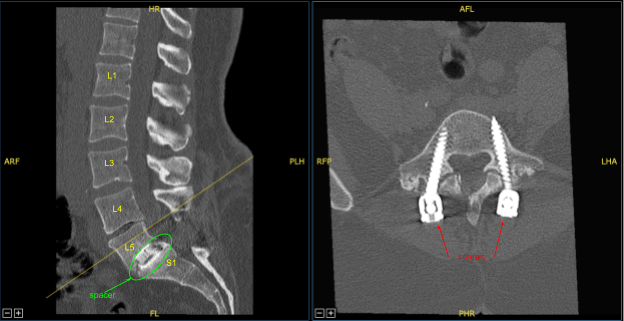

The patient presented to the office status post two previous lumbar surgeries performed by another provider including L5-S1 discectomy and L5-S1 TLIF. They developed recurrent back and lower extremity pain and symptoms and imaging showed adjacent segment disease with L4-L5 disc herniation, stenosis, as well as pseudarthrosis at L5-S1.

Locking caps at L5 and S1 were removed. The rods were removed. The screws were checked and were found to be tight and therefore were left in place. Next, the fixed neuronavigation arrays for the right posterior-superior iliac crest with two Schanz pins. Sterilely draped the patient to obtain the CT scan.

Transferred the data to the neuronavigation computer and image guided neuronavigation techniques were utilized for placement of the bilateral L4 pedicle screws which was accomplished by decorticating electric high-speed drill, cannulating the pedicles with the navigated pedicle finder, sounding for breaches, and measuring the depth using 5.5-mm tap and placing 6.5×45 mm titanium pedicle screws under neuronavigation guidance without difficulty. Neuromonitoring signals were table throughout.

Demineralized bone matrix allograft was placed into the interspace and then titanium expandable interbody device was placed under fluoroscopic guidance after sterilely draping the C-arm unit. AP and lateral imaging showed correct positioning and then the cage was expanded to the proper fit and the subsequent x-ray showed good positioning both in the midline and anteroposterior.

Next, a new CT scan was obtained, which showed correct positioning of the new pedicle screws and interbody spacer. Bilateral transverse processes of L4, L5, and lateral ala were decorticated for arthrodesis. Pre-cut, pre-contoured rods reflected and placed across the tulips from L4 to S1 and secured with locking caps and finally tightened with the torque and anti-torque device.